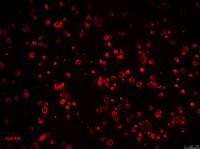

SCC107 Sigma-AldrichCR4 Human Colorectal Cancer Cell Line

CR4 is a unique, cancer stem cell (CSC) enriched, human colorectal cancer cell line useful for CSC-targeted drug development and research focused on cancer cell and CSC biology.

More>> CR4 is a unique, cancer stem cell (CSC) enriched, human colorectal cancer cell line useful for CSC-targeted drug development and research focused on cancer cell and CSC biology. Less<<Recommended Products

| CR4 Human Colorectal Cancer Cell |